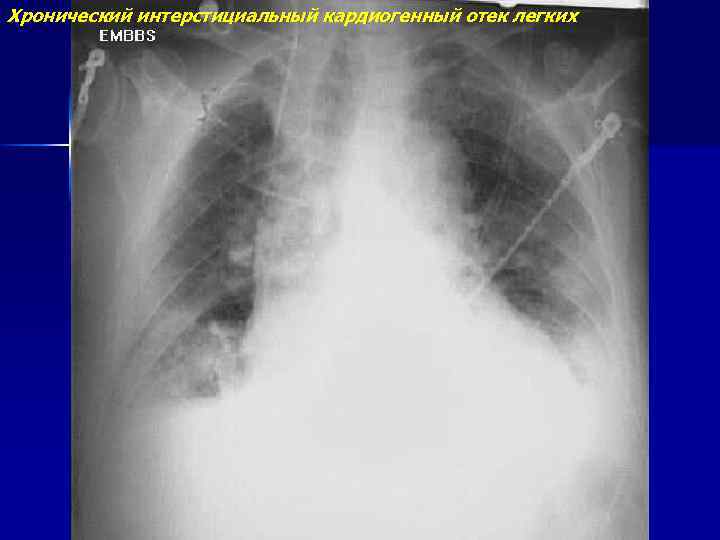

Хронический интерстициальный кардиогенный отек легких